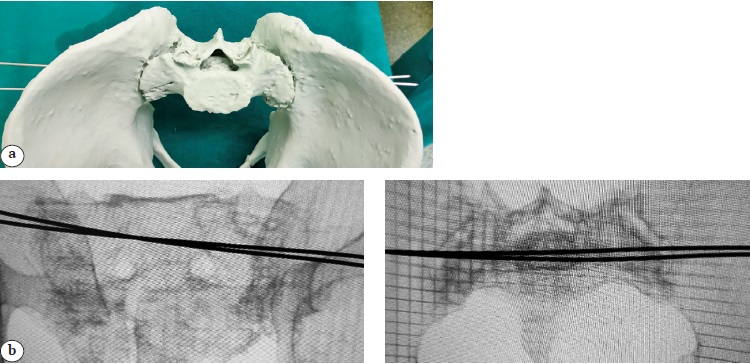

The physical 3D model was then sterilized using low-temperature plasma to allow intraoperative interaction with it (Figure 4).

Figure 4 (a). Process and result of using 3D model: a — model prepared for sterilization;

Figure 4 (b, c). Process and result of using the 3D model: b — radiographic control during surgery; c — postoperative X-ray